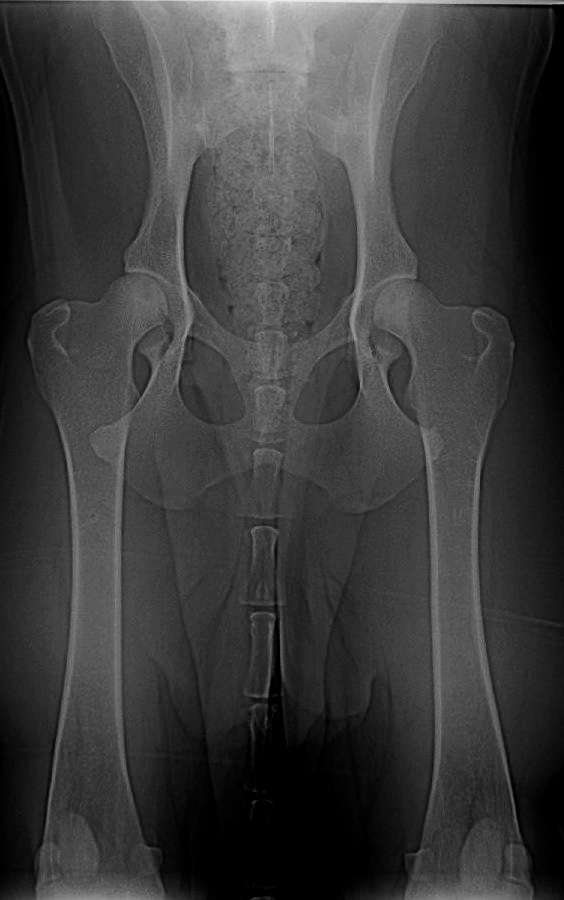

Znovu na rentgenu jsme byli ve zhruba čtyřech letech, kdy Grif prodělal amputaci plovací blány, protože se mu po zánětu udělala boule velikosti velkého vlašského ořechu. Rentgen, který zde vidíte je poslední, ze skoro sedmi let, kdy jsme byli na operaci s předním loktem, artrózu bylo nutné odfrézovat. Ano, to byla poslední zatím neoperovaná noha. Pro přehled je vedle další rentgen zdravého psa (mladého leonbergera). Prohlédněte si oba klouby. (Kliknutím otevřete obrázky v plné velikosti).